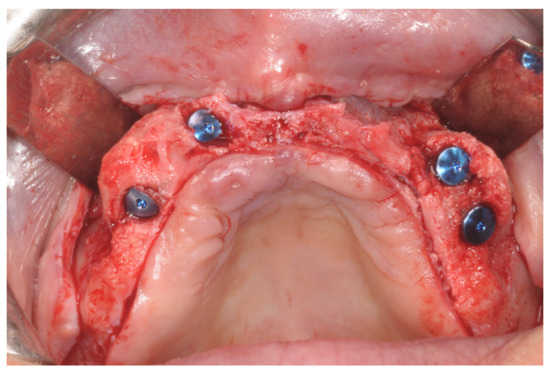

Patients rinsed with a chlorhexidine mouthwash (0.2%) for 1 min immediately prior to the intervention. Local anesthesia were administered using mepivacaine with adrenaline at ratios of 1:100,000 or 1:50,000. Crestal incisions were made with releasing incisions far away from the future membrane positioning and full thickness flaps were elevated. After the meticulous removal of all residual soft tissues in the regenerating site, copious bleeding was induced using a bone scraper (Safescraper Curve TWIST, META, Reggio Emilia, Italy) (Figure 1). A prosthetically guided implant placement was performed following the instructions of manufacturer (Thommen Medical, Grenchen, Switzerland). Only 1 patient had implants placed 9 months after bone augmentation because the initial bone thickness did not permit the primary stabilization of the implant fixtures (Figure 2, Figure 3, Figure 4, Figure 5, Figure 6, Figure 7 and Figure 8).

Figure 4. Placement of the graft and of the non-resorbable membranes, fixed with pins.